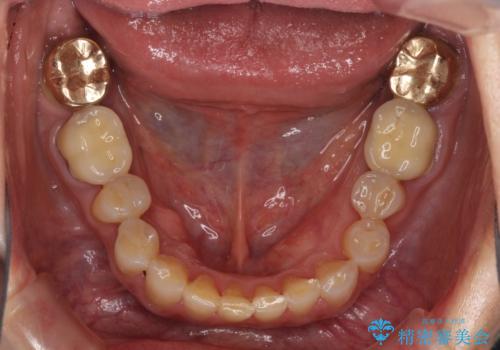

- 全顎的な歯肉からの出血と前歯の形態を気にして来院された患者様です。

診査の結果、上顎奥歯を中心に深い歯周ポケットが認められたため、歯周ポケット除去を目的とした歯周外科処置を行うこととしました。

また、前歯のブリッジへの咬合力の負担が大きく、土台となっている歯が揺れてしまっていたため、インプラント埋入により奥歯への負担を軽減することとしました。